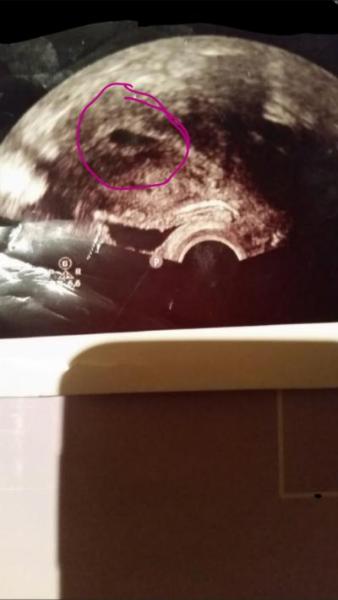

Ich muss vorab sagen das ich schon 4 wundervolle Kinder habe und wir uns dann nun vor 9 Monaten entschieden haben das ich mich sterilisieren lassen das habe ich dann auch gemacht nach unseren letzten tochter (da wir keine Kinder mehr möchten bzw wollten ) Nun habe ich Anzeichen das ich schwanger bin (Periode sei 2 Wochen ausgeblieben ) waren dann heute auch im kh da meine ks narbe auch dicker geworden ist ... Die ärtzin machte Ultraschall und sagte bei ihn baut sich eine Schwangerschaft auf  (Natürlich wenn es so ist behalten wir es das ist keine Frage )nur sollten wir jetzt uns darauf einstellen das ich schwanger bin  PS der ss test war negativ im kh und darauf sagte sie das wäre normal

Bild zu Brauche dringend ein Rat - Schwanger - wer noch? Rund um die Schwangerschaft